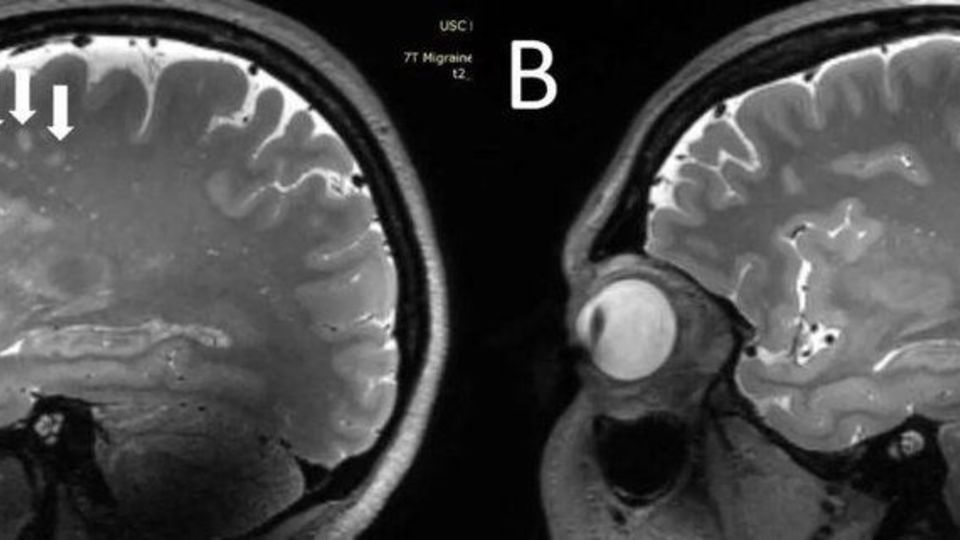

ژو و همکارانش، به دنبال آن هستند تا ارتباط میان میگرن وبزرگ شدن فضاهای اطراف عروقی را درک کند. این محققان با بهرهگیری از MRI ۷T با وضوح فوقالعاده بالا، به مقایسه ساختاری تغییرات میکروواسکولار (رگهای خونی بسیار ریز) در انواع مختلف میگرن پرداختند. ژو در این رابطه گفت:« این اولین بررسی با استفاده از MRI با وضوح فوقالعاده بالاست که در آن به بررسی تغییرات میکرو واسکولار مغز در پی بروز میگرن، بهویژه در فضاهای اطراف عروقی پرداخته میشود. از آنجا که MRI ۷T قادر است تا تصاویری با وضوح و با کیفیت به مراتب بالاتری نسبت به دیگر دستگاههای MRI از مغز ارائه دهد، میتوان از این دستگاه برای تشخیص تغییرات جزئیتر و ریزتری که بعد از بروز میگرن در بافت مغز ایجاد میشود، بهره برد.»

محققان، در جریان این بررسی فضاهای بزرگ شده اطراف عروقی را در سنتروم سِمی اوال (بخش مرکزی ماده سفید مغز) و غدههای قاعدهای را اندازهگیری کردند. افزایش و شدت ماده سفید مغز (ضایعهای که در MRI به روشنی مشخص است) با بهرهگیری از مقایس Fazekas اندازهگیری شد. خونریزیهای میکروبلید مغزی (خونریزیهای بسیار ریز در مغز) با خونریزیهای میکروبلید در آناتومی بدن با مقیاس رتبهبندی، طبقهبندی شدند. محققان در عین حال دادههای بالینی افراد از جمله دوره بیماری و شدت آن، نشانهها و علائم در هنگام انجام اسکن و وجود هاله و منطقه سردرد فرد را نیز جمعآوری کردند.

تجزیه و تحلیلهای آماری حکایت از آن داشت که تعداد فضاهای بزرگ شده اطراف عروقی در مرکز سِمی اوال مغز افراد، در بیمارانی که میگرن داشتند، به مراتب بیشتر از افراد سالم بود. به علاوه کمیت فضاهای بزرگ شده اطراف عروقی در مرکز سِمی اوال با عمق ماده سفید، از نظر شدت جدی بودن در بیماران میگرنی در ارتباط است.

ژو ادامه داد:« ما در تحقیقات درباره میگرن مزمن و میگرن اپیزودیک بدون هاله به این نتیجه رسیدیم که در هر دو دسته افراد مبتلا به این نوع میگرنها، فضاهای اطراف عروقی در مرکز سِمی اوال بزرگتر بودند. اگرچه ما هیچ تغییر قابل توجهی در شدت ضایعات بخش سفید مغز در افراد مبتلا به میگرن و افراد بدون میگرن پیدا نکردیم، ولی این ضایعات بخش سفید مغز به طور قابل توجهی با وجود فضاهای بزرگ شده اطراف عروقی مرتبط بودند. این بدان معناست که تغییرات در فضای اطراف عروقی، ممکن است منجر به افزایش ضایعات بیشتری در بخش سفید مغز شوند.»